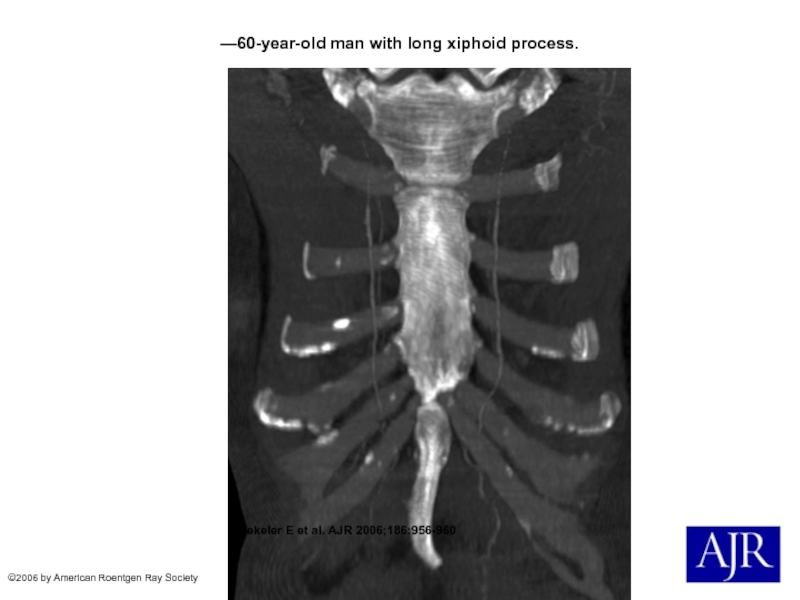

Слайд 12—60-year-old man with long xiphoid process.

Yekeler E et al.

AJR 2006;186:956-960

©2006 by American Roentgen Ray Society

—60-year-old man with long xiphoid process. Yekeler E et al. AJR 2006;186:956-960©2006 by American Roentgen Ray Society